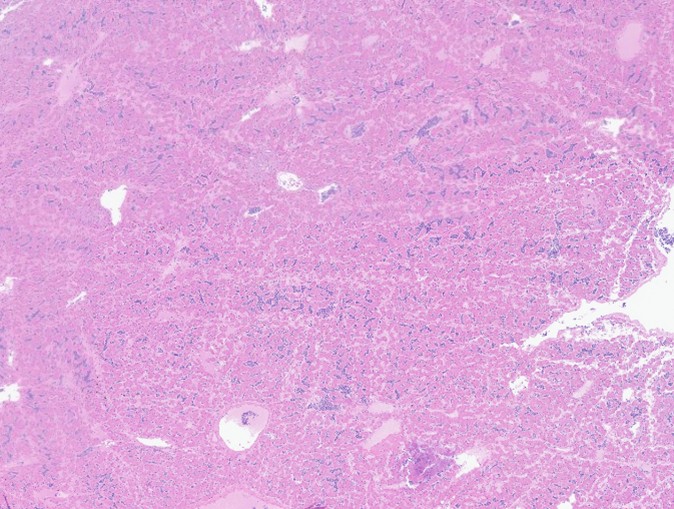

The bronchi and parabronchi contain numerous large syncytia with large amphophilic-to-eosinophilic intranuclear inclusions that marginalize the chromatin. Bronchi and parabronchi also often contain foamy macrophages, pale basophilic mucus, homogeneously eosinophilic edema fluid, fibrin, cellular debris, and sloughed necrotic epithelial cells.

Lung: Pneumonia, histiocytic, with syncytia and intranuclear inclusion bodies

Respiratory herpesviruses have been de-scribed in Indian ringneck parrots as early as the 1990s.4,8 Similar gross and microscopic le-sions have been reported in psittacines infected with PsAHV3 and PsAHV5, including the formation of large syncytia and intranu-clear inclusions throughout the respiratory tract.2,6,7 Thus far, PsAHV5 has been detected in Indian ringneck parakeets, Alexandrine parakeets, Bourke’s parrots, and possibly eclectus parrots. Concurrent infections, such as Aspergillosis, are common.2

The JPC’s own Dr. Elise LaDouceur moder-ated this year’s avian-focused seventeenth conference. This first case provided participants with a panoply/salmagundi/”dog’s breakfast” of tissues to sort through to achieve a diagnosis. The characteristic intranuclear viral inclusion bodies of herpesvirus were best seen in the air sac respiratory epithelium, which also rewarded conference-goers with some exceptional viral syncytia. Of the potential herpesviral culprits, psittacine al-phaherpesviruses (PsAHV) 1, 3, and 5 have been reported in psittacine species, including Indian ringneck parakeets, and PsAHV-5 was isolated by the contributor in this case. The contributor provided some beautiful electron microscopy (EM) photos from this bird that demonstrated intranuclear herpesviral virions, with some virions budding from the nuclear envelope to become enveloped themselves, and others hanging around the rough endo-plasmic reticulum (RER) to acquire additional proteins. The JPC is grateful to the contributor for providing these excellent educational images!

Participants also noted the characteristic “freeze-thaw” artifact of the liver that is best appreciated at low magnification and causes acicular clefts filled with pale eosinophilic fluid. This is a classic artifact to be aware of!